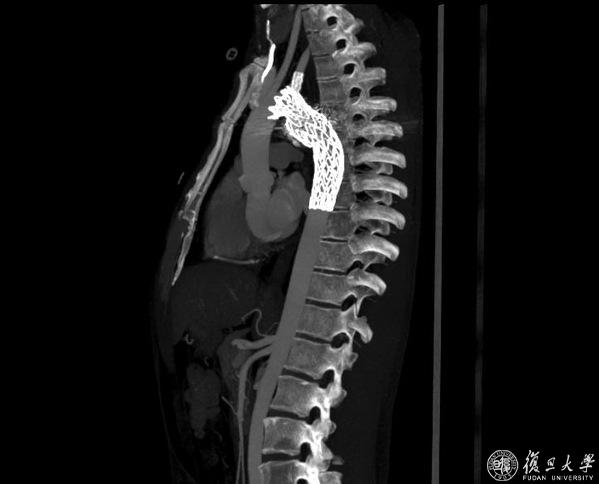

4月28日下午,血管外科符伟国教授、董智慧教授、石赟教授、方刚医生、王峰医生、邹凌威博士共同为格桑旦增实施了胸主动脉腔内修复术,同时,为尽量保留较优势的左侧椎动脉,采用了原位开窗技术重建左锁骨下动脉,使用了符伟国教授原创设计的Fustar可调弯鞘等专用器材。该核心器械为主动脉弓部腔内病变的患者带来了更安全、有效的腔内介入解决方案,已获国际发明专利,并通过美国FDA和欧盟CE认证,销往欧美14个国家和地区。

最终,手术顺利完成,即刻造影显示动脉瘤已消失,胸主动脉弓上分支血管血流畅通。术后,格桑旦增咯血症状消失,术后一天即可下床活动,恢复良好,目前已顺利出院。出院两周之后的复查中显示支架保持通畅,动脉瘤隔绝良好,瘤腔内已完全血栓化。格桑旦增也终于松了一口气,可以放心地长途飞行返回西藏了。